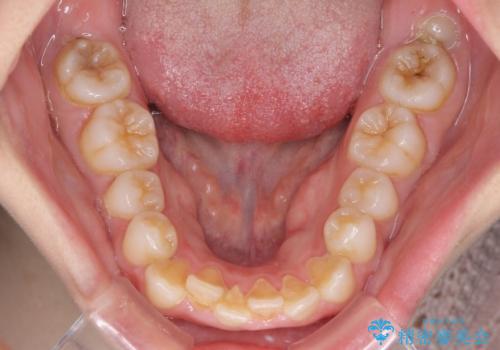

- 前歯が突出しているために口が閉じられないとのことで来院された患者様です。

上下ともに顎が小さく、歯列が前方に突き出していたため、上下左右の第一小臼歯4本を抜歯し、口元の突出感を改善していくこととしました。